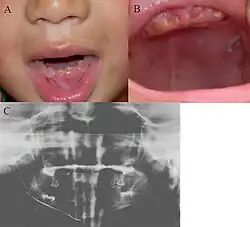

| Oral photographs from an individual with Dentinogenesis imperfecta | |

People with this condition have abnormal enamel, short and narrow roots, and can lack nerves. This condition can cause teeth to be discolored (most often a blue-gray or yellow-brown color) and translucent, giving teeth an opalescent sheen.[2][3][8][5][9] Teeth are also less mineralized than normal, making them prone to rapid wear, breakage, and loss.[2][3][4][5][8] These problems can affect primary (baby) teeth alone, or both baby teeth and permanent (adult) teeth, with the primary teeth usually more severely affected.[5][8]

- Discolored teeth - teeth may be amber, brown, blue or opalescent

- Bulbous shape to the tooth crown due to cervical constriction

- Tooth wear/Non-carious tooth surface loss (NCTSL) - due to the poorly mineralized dentin, the enamel of the tooth is unsupported and subsequently shears or chips off as it is subjected to occlusal (biting) forces. This exposes the underlying less mineralized dentin which is less resistant to wear. Therefore, features of abrasion and attrition may become apparent.

The primary (baby) teeth are usually more severely affected than permanent (adult) teeth.[3][5][8]

Enamel is usually lost early because it is further inclined to attrition due to loss of scalloping at the dentinoenamel junction (DEJ). It was suggested that the scalloping is beneficial for the mechanical properties of teeth as it reinforces the junction between enamel and dentin.[15] However, the teeth are not more susceptible to dental caries than normal ones.

Note that, although dentin exposure is a common clinical finding, individuals with dentinogenesis imperfecta usually do not experience tooth sensitivity as the exposed dentin is typically sclerosed (hardened), thereby appearing glassy/shiny.[2]

- Bulbous shape of tooth crown with pronounced cervical constriction

- Small pulp, or total pulp obliteration

- Small or obliterated root canal

- Narrow and small roots

- Periapical radiolucency without any evidence of clinical pathology such as tooth decay (dental caries)[2][3][5][14]